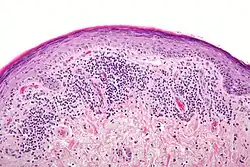

Histologicamente, observa-se superfície epitelial ortoqueratinizada ou paraqueretinizada, degeneração ou liquefação da camada basal do epitélio, papilas epiteliais em forma de serrilhado, infiltrado linfocitário e macrofágico em banda subepitelial.

Histopatologia

É típica, com degeneração hidrópica das células da camada basal levando a formação de queratinócitos necróticos (corpos colóide), hipergranulose focal, hiperceratose ortoceratótica, acantose em “dentes de serra”, incontinência pigmentar e infiltrado linfocitário em faixa na derme. A imunofluorescência direta mostra depósitos globulares de IgM, e ocasionalmente IgG e IgA, representando queratinócitos apoptóticos. Observa-se depósito de fibrina na junção dermo-epidérmica.[9]